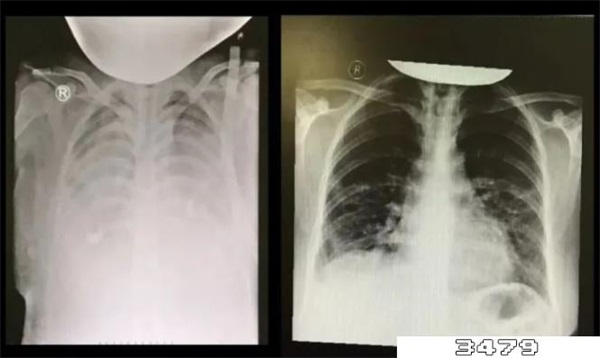

白肺的症状通常表现为严重的缺氧,且伴有胸闷、紫绀、呼吸困难、呼吸窘迫、严重低血氧症、剧烈咳嗽等,严重者可能会出现呼吸衰竭,甚至是昏迷。感染新冠病毒后,如果出现类似的症状,应及时到医院呼吸内科就诊,同时辅以肺功能检查、胸部X线检查、CT检查等明确诊断,并在医生指导下进行治疗。